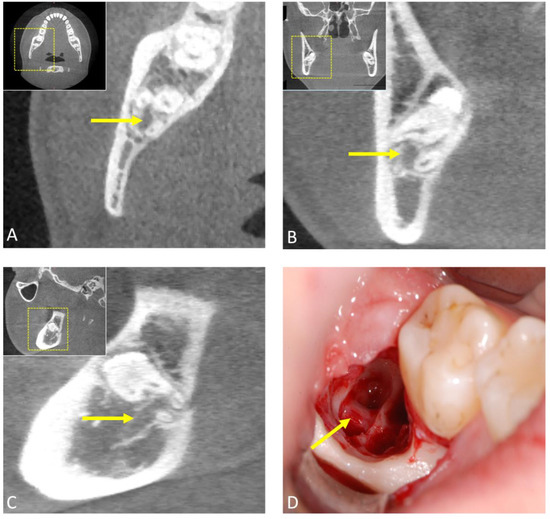

2.2. Computed Tomography (CT)

2.3. Cone-Beam Computed Tomography (CBCT)

- Nakamori, K.; Tomihara, K.; Noguchi, M. Clinical significance of computed tomography assessment for third molar surgery. World J. Radiol. 2014, 6, 417–423. [Google Scholar] [CrossRef]

- Susarla, S.M.; Dodson, T.B. Preoperative computed tomography imaging in the management of impacted mandibular third molars. J. Oral Maxillofac. Surg. 2007, 65, 83–88. [Google Scholar] [CrossRef]

- Xu, G.Z.; Yang, C.; Fan, X.D.; Yu, C.Q.; Cai, X.Y.; Wang, Y.; He, D. Anatomic relationship between impacted third mandibular molar and the mandibular canal as the risk factor of inferior alveolar nerve injury. Br. J. Oral Maxillofac. Surg. 2013, 51, e215–e219. [Google Scholar] [CrossRef] [PubMed]

- Ohman, A.; Kivijärvi, K.; Blombäck, U.; Flygare, L. Pre-operative radiographic evaluation of lower third molars with computed tomography. Dentomaxillofac. Radiol. 2006, 35, 30–35. [Google Scholar] [CrossRef]

- Lübbers, H.T.; Matthews, F.; Damerau, G.; Kruse, A.L.; Obwegeser, J.A.; Grätz, K.W.; Eyrich, G.K. Anatomy of impacted lower third molars evaluated by computerized tomography: Is there an indication for 3-dimensional imaging? Oral Surg. Oral Med. Oral Pathol. Oral Radiol. Endod. 2011, 111, 547–550. [Google Scholar] [CrossRef]